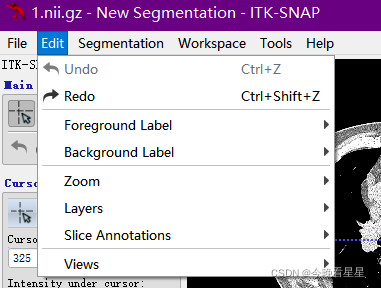

1.3 Edit编辑菜单

Undo撤销,Redo重做Foreground Label与Background Label是不同标注之间的关系

Zoom对区域进行缩放Layer处理添加的不同的层,比如:CT扫描的不同段Slice Annotations -> Toggle....可以去掉视图的标注信息,Slice Annotations -> Annotation Preference可以对标注的格式进行设置